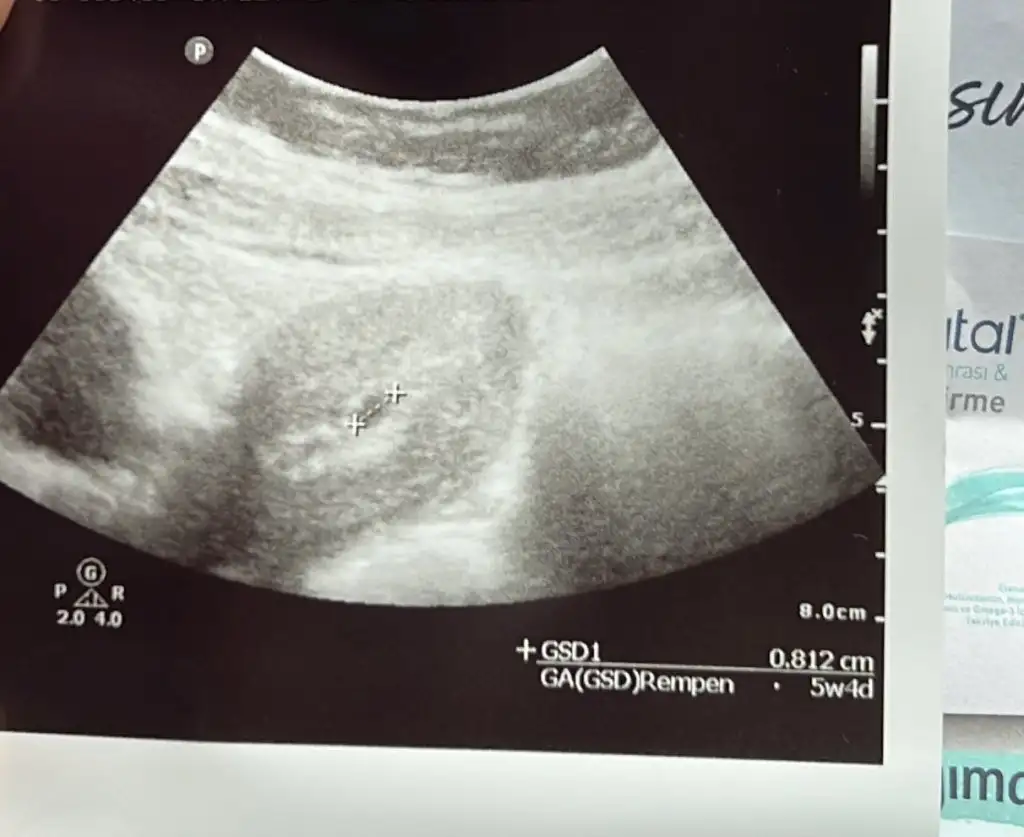

Çok güzel canım ölçümümüz yakın birbirine benim de 0.88cmSelam kızlaarBugün keseyi gördük. Normalde 5+1 im ama doktor 5+4 gözüküyor dedi. kanama alanı gördü ama zararlı değil yerleşmeyle alakalı da olabilirmiş. Haftaya Cumartesi tekrar gideceğim kalp atışını duymaya. Tahlillerimi de verdim.

Çok güzel canım ölçümümüz yakın birbirine benim de 0.88cm

Ben de siz söyleyince baktım 5 haftalikken 6cm imiş minikbugün 5+3 mercimek büyüklüğünde